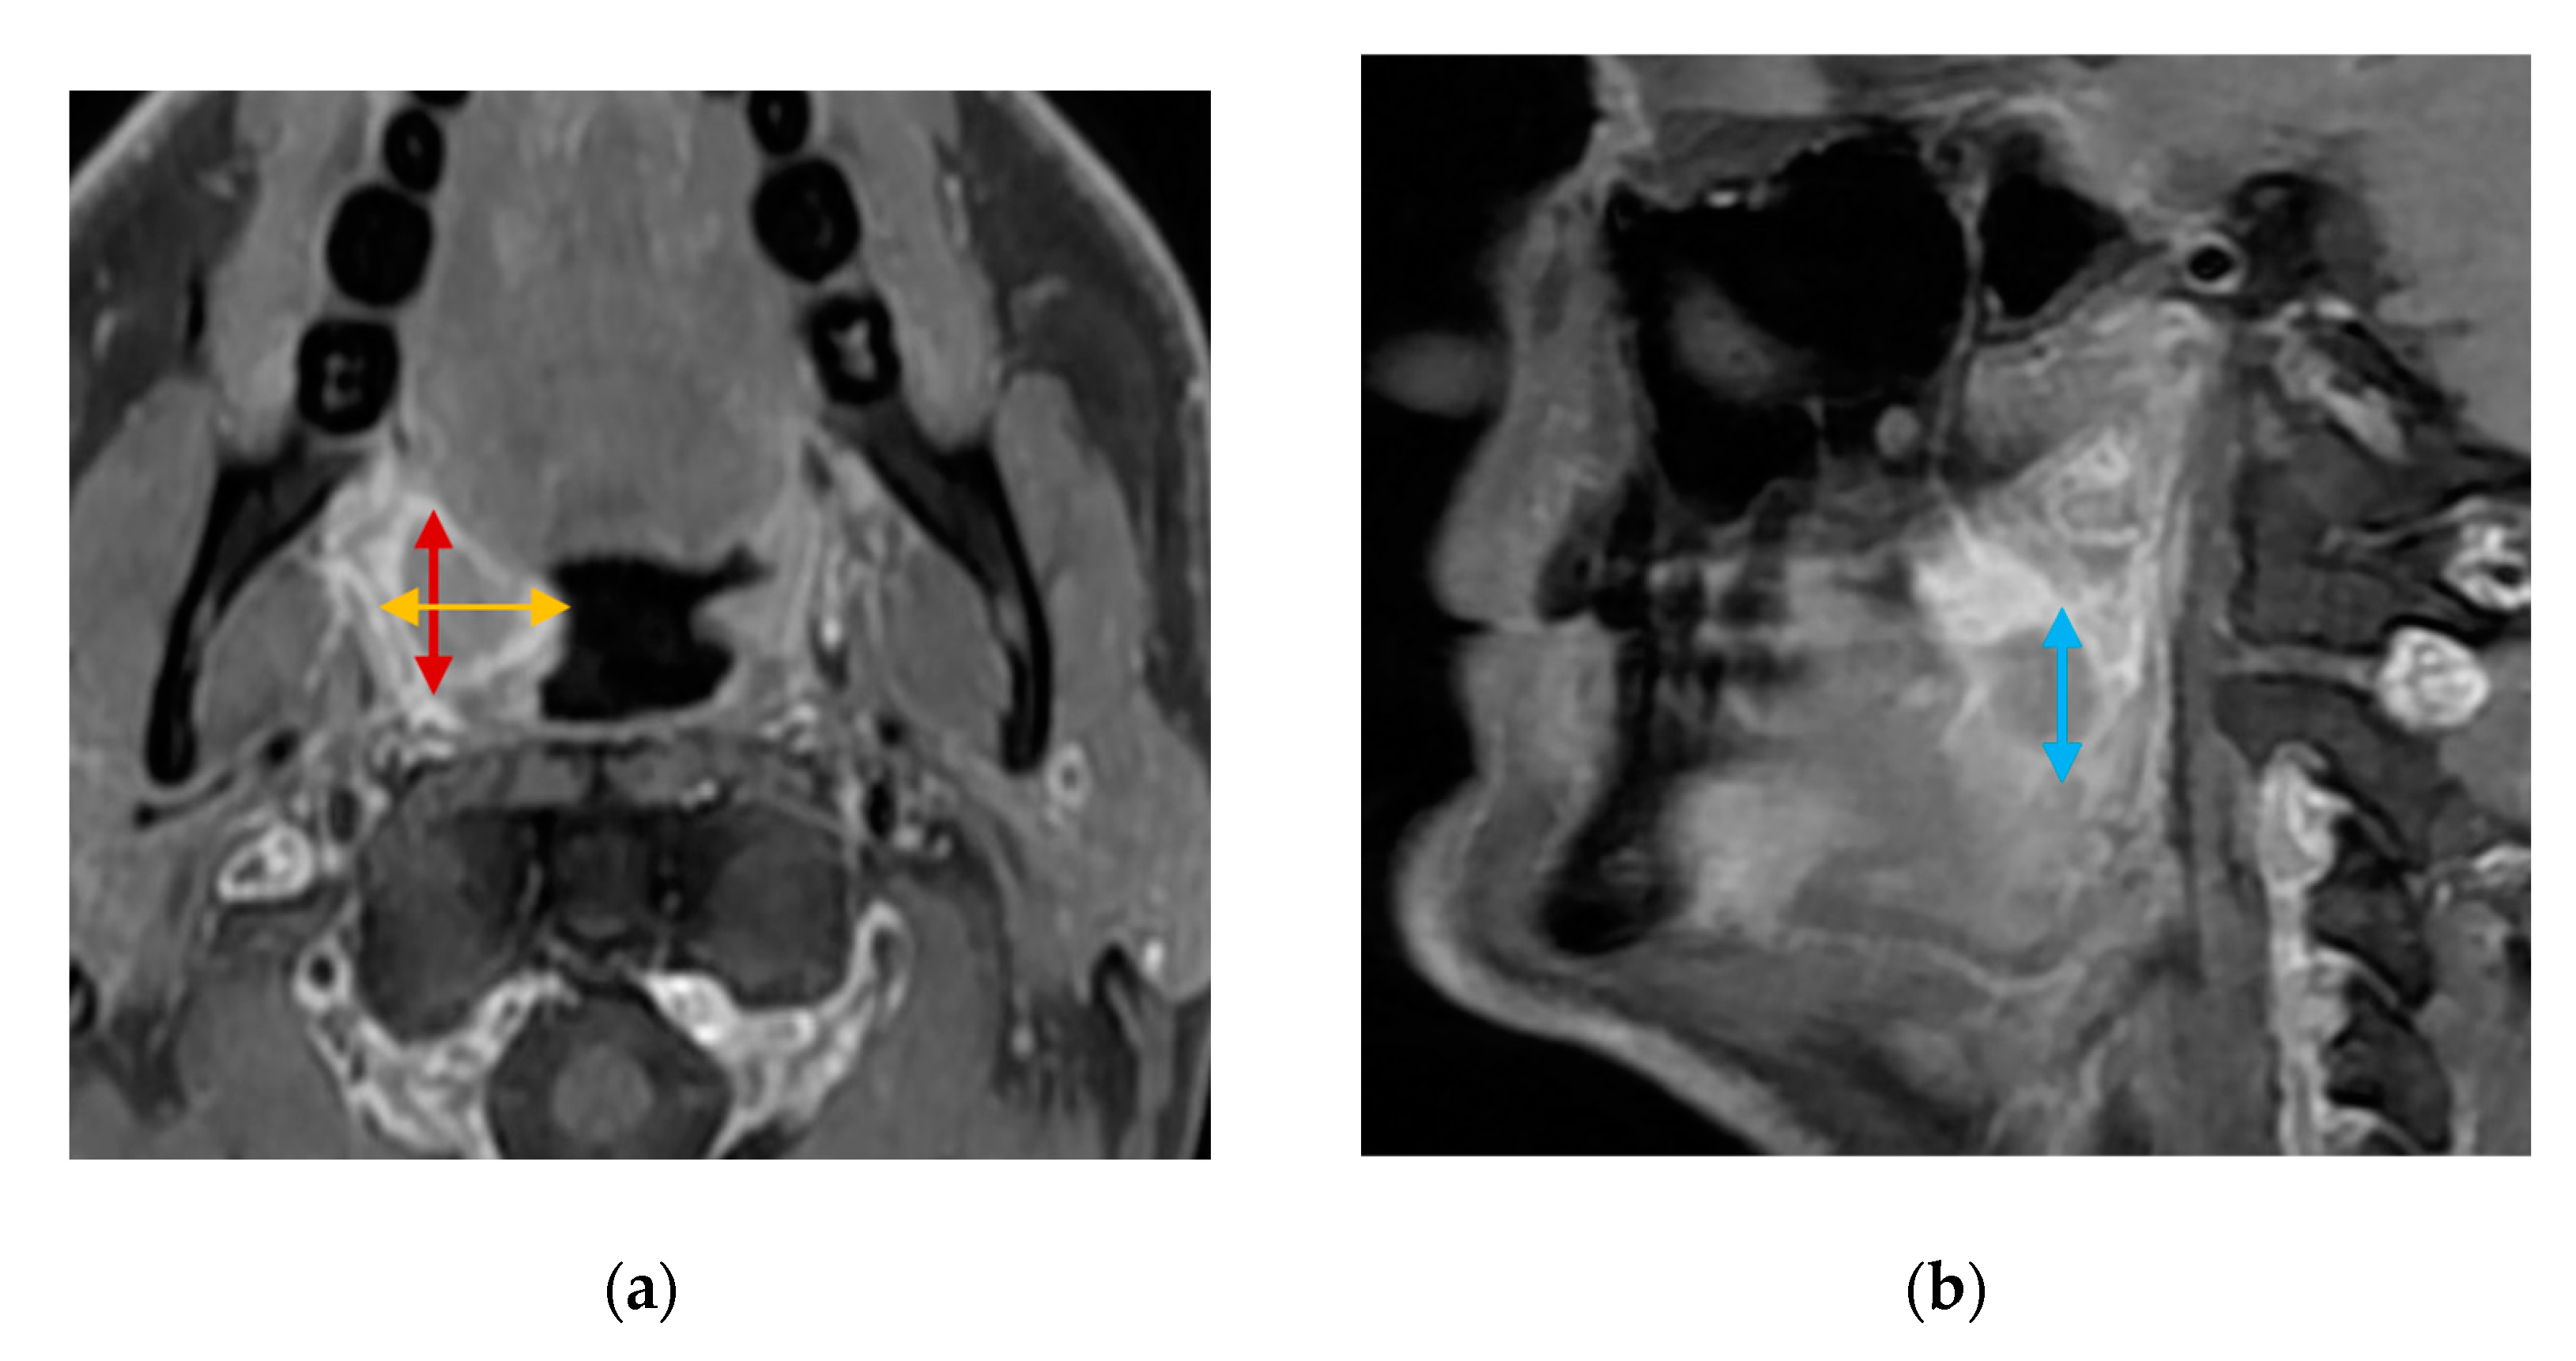

For transcervical US, the tongue and lingual tonsils are visualized using a curved low-frequency transducer placed on the suprahyoid region in a transverse plane. A swipe from the chin to towards the hyoid bone is performed (Figure 3a). The probe is then rotated 90 degrees clockwise to the sagittal plane and two consecutive midline-to-lateral swipes are performed for each side of the base of tongue (Figure 3b). Similarly, the palatine tonsils are visualized in two planes in the submandibular gland region (Figure 3c,d) [20]. The quality of both transoral and transcervical US scans will be rated using a 5-point Likert scale (1—Very poor; 2—Poor; 3—Fair; 4—Good; 5—Excellent) [35]. Patient-reported discomfort from transoral US will be quantified using an 11-point numeric rating scale from 0 (no discomfort) to 10 (worst discomfort imaginable).

Figure 3. Transcervical US of the palatine and lingual tonsils. Transducer orientations are represented on the top right of each image with a white arrow representing the swiping directions: (a) oblique transverse US image of the base of tongue with the geniohyoid (GHM), genioglossus muscles (GGMs), intrinsic tongue muscles (ITMs), hyoglossus muscle (arrowhead), oral surface of the tongue (dashed line), and a hypoechoic endophytic tumor in the right base of tongue (dotted outline). The mediolateral diameter of the tumor is shown (orange bi-directional arrow); (b) sagittal US image of the same tumor with the hyoid bone’s acoustic shadow shown (white outline)—craniocaudal (blue bi-directional arrow) and anteroposterior (red bi-directional arrow) tumor diameters; (c) Oblique transverse US image of a benign hyperplastic palatine tonsil (PT, dotted outline), the submandibular gland (SMG), tongue, and mediolateral diameter of the PT (orange bi-directional arrow); (d) sagittal US image of the same PT with the mandible’s acoustic shadow shown anteriorly as a landmark for the anteroposterior diameter (red bi-directional arrow). The craniocaudal diameter (blue bi-directional arrow) of the PT is parallel to the hyperechoic mucosal surface seen below the tonsil.

The greatest tumor diameters in three dimensions and an ultrasonographic T-stage will be registered considering tumor invasion of deep structures according to the UICC8 staging system. Transcervical US will be used to measure primary oropharyngeal tumors that are larger than the transoral US transducer’s field-of-view (Figure 3). We will register whether the transoral US or transcervical US was superior in terms of tumor measurement and invasion.